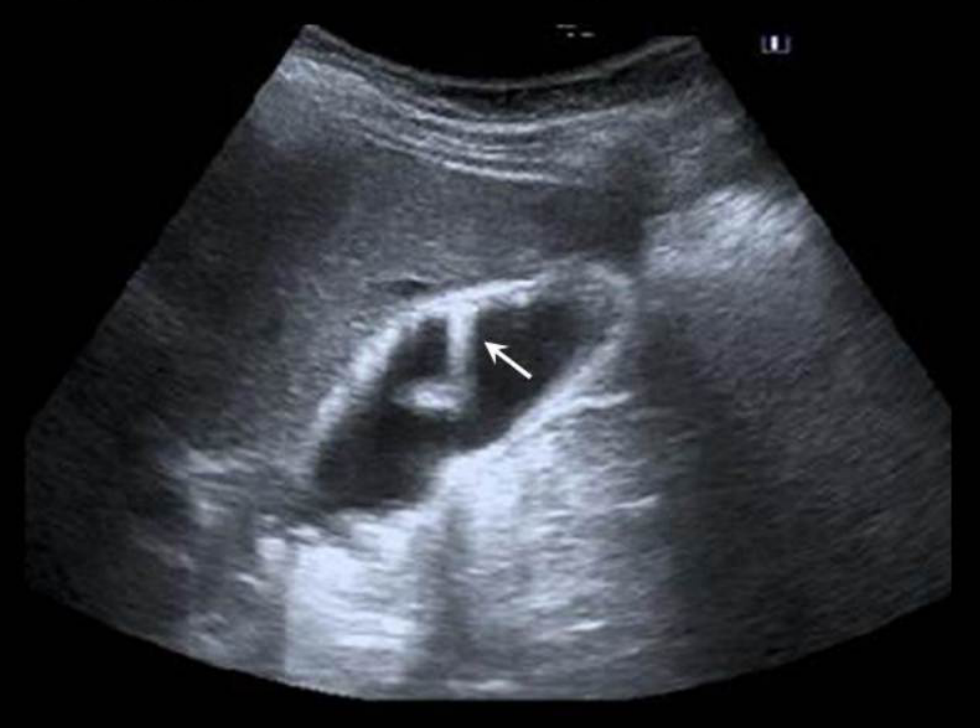

Name this artifact.

What is the cause of the artifact?

Mirror image artifact: Created when sound reflects off a strong reflector and is redirected toward a second structure (target), where it then reflects back to the first reflector, then back up to probe. This creates a second image of the target in the path of the original beam and deeper than the actual target